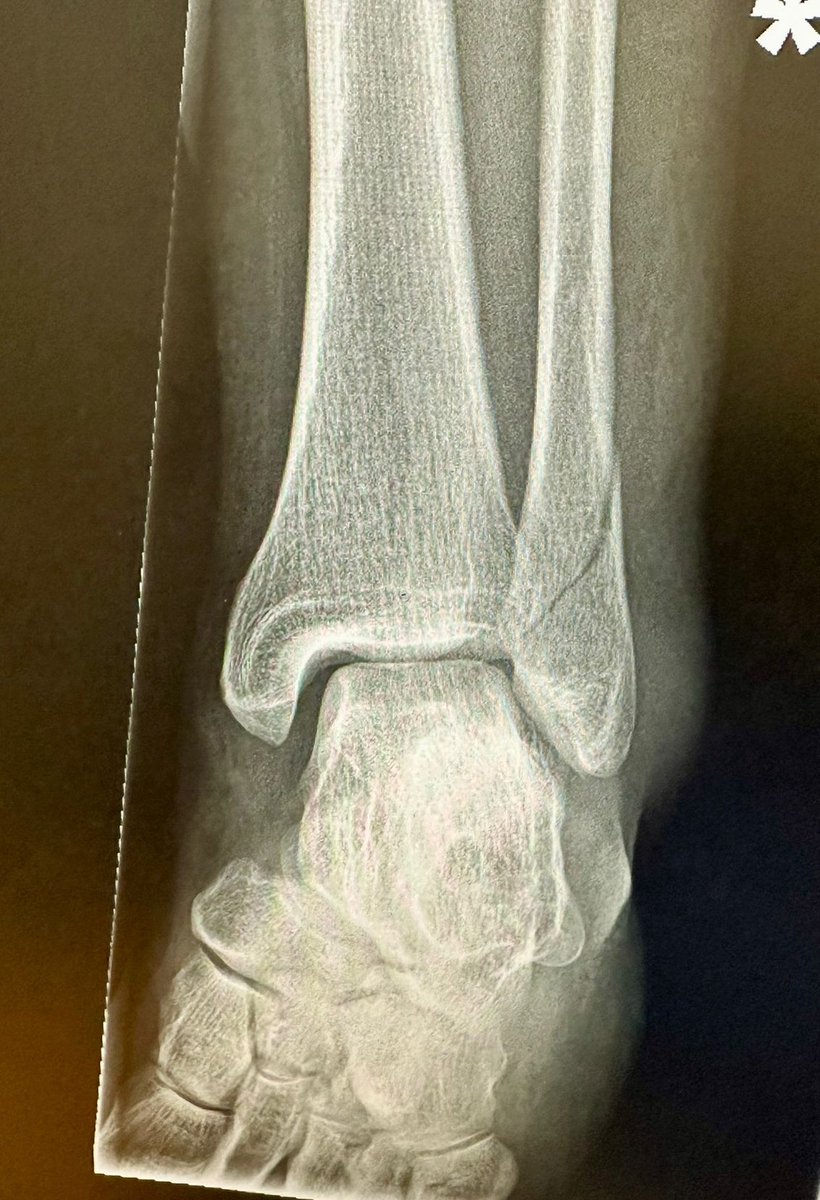

Delighted 35yr tennis player who had 2 x ACL ruptured + meniscus op consent ✅